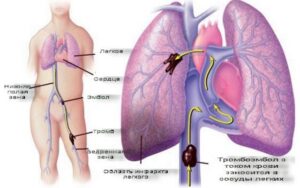

Туберкулез легких является следствием перенесенной ранее туберкулезной инфекции, которая реактивировалась из-за сбоя иммунной системы. Туберкулез — это закрытый казуистический узел в легком размером более 12 мм. Характерной особенностью процесса является его длительное и мало симптоматическое течение, основные причины и диагностические симптомы которого можно найти в этой статье. Что это такое? Туберкулема (от латинского tuberculum — …